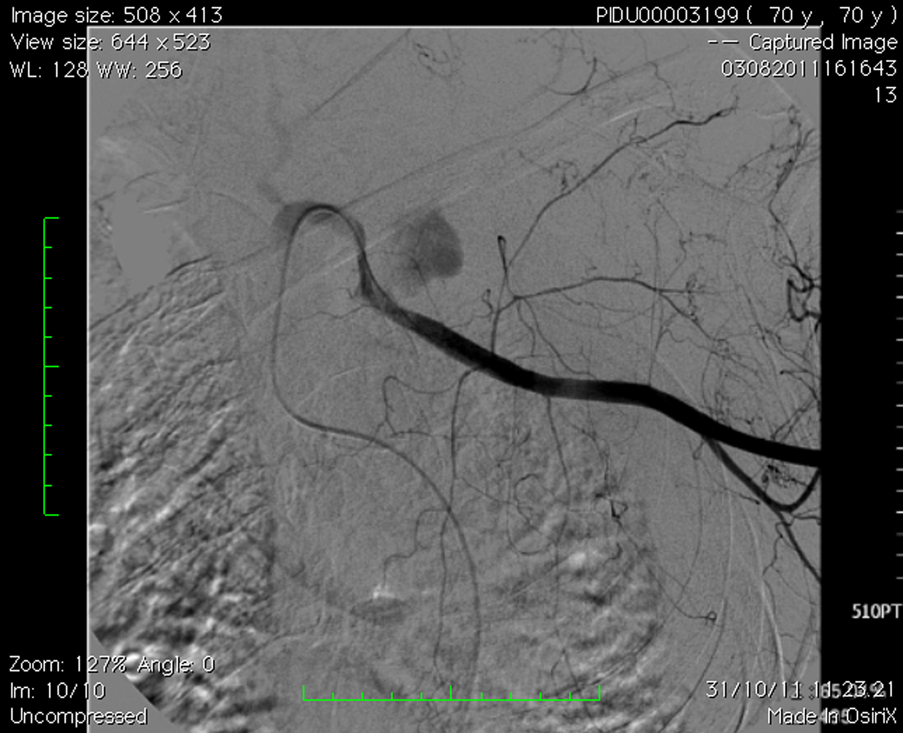

No pneumothorax was present on XR. - Further imaging: US / Angiogram

-

left subclavian arterial bleeding, 3 cm after homolateral vertebral artery. - CT

CT shows left subclavian arterial bleeding and the left midshaft clavicular fracture.